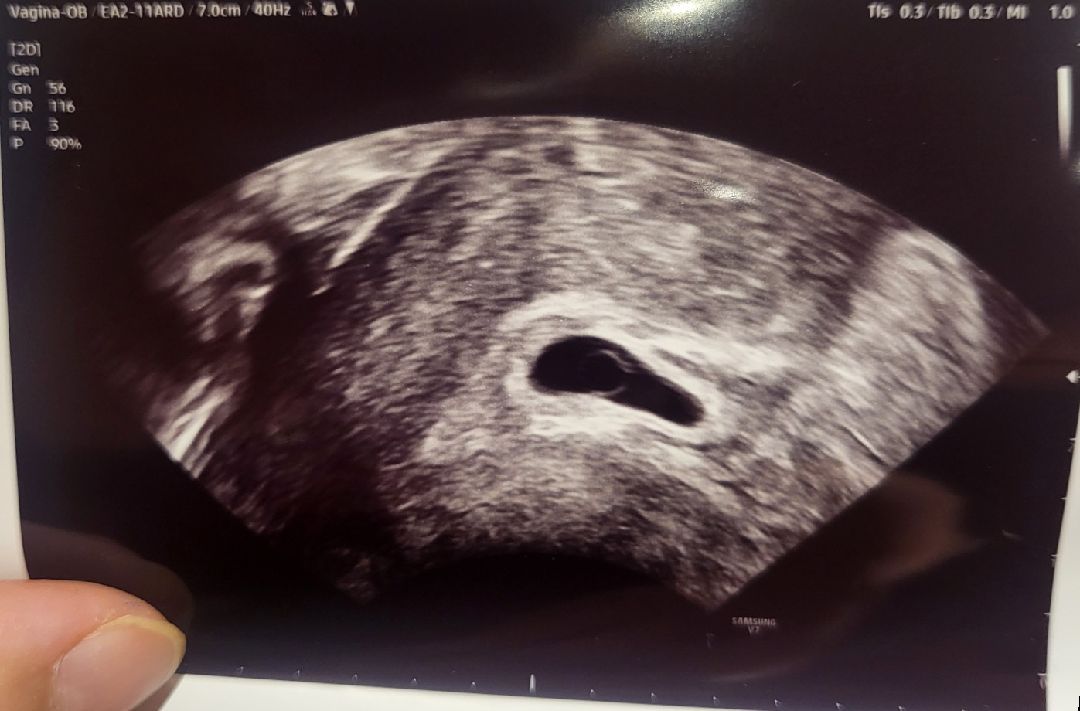

어제 7주0일 심장깜빡임못봤어요ㅜ

어제 7주0일인데 깜빡임못본거면 예후가안좋은거겠죠?;;; 난황도 6주2일에 보긴봤었어요ㅜ 너우태아도안보이고너무깨끗해보이죠?;;